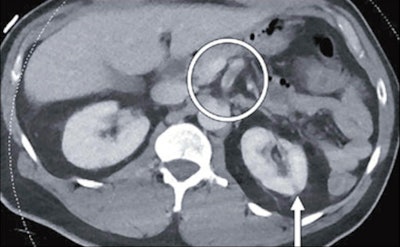

The group found that nine of patients (11%) with COVID-19 had thromboembolic findings on imaging; of these, five had medium to large arterial thrombi. Occurrence of thromboembolic findings in COVID-19 patients compared with those without the disease was statistically significant, at p = 0.02.

"Patients with solid-organ infarction had patent vasculature, suggesting the infarction may have resulted from microthrombi," the group noted.

"COVID-19 may present with medium to large arterial and venous abdominal and extremity macrothrombi," it concluded. "Radiologists should raise concern for COVID-19 when identifying thromboembolic abdominopelvic findings during this pandemic."